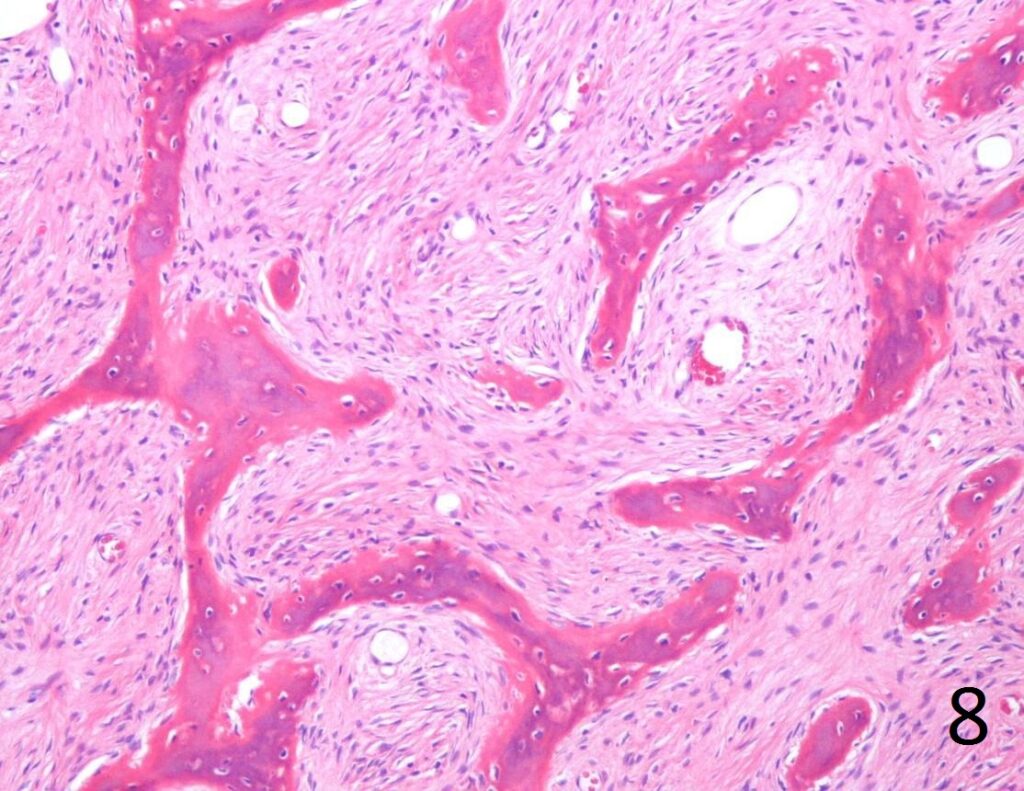

• Combination of bland hypocellular fibrous tissue with small fragments of woven bone without visible rimming by osteoblasts(Fig. 7-8) .

• The trabecule are common referred as Chinese characters, or resembling “Cs”and “Os”. Also may be called Alphabet Soup. This arrangement may mimic the appearance of Paget’s diseases

• Trabeculae are not lined with oteoblasts.

Fig. 8. Microscopic: Low power photograph of fibrous dysplasia shows a combination of bland fibrous tissue with small fragments of woven bone. The lesion is hypocellular with small uniform fibroblasts. There are spicules of bone that are not lined by osteoblasts.